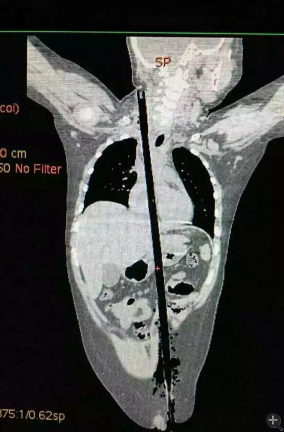

據(jù)相關(guān)知情人介紹,受傷男童24日晚在家中與小朋友一塊兒在墻頭上玩耍時(shí),一不小心從高墻上跌落到了鄰家花圃中,讓人觸目驚心的是,該男童正好跌到了花圃中的一支長(zhǎng)約63厘米,直徑約1.5厘米的竹棍上,竹棍自孩子的左側(cè)大腿根部直接插入腹腔并入胸腔直至右側(cè)頸部。

市兒童醫(yī)院組織專家團(tuán)隊(duì)對(duì)孩子的病情進(jìn)行檢查、評(píng)估后發(fā)現(xiàn),竹棍由患兒左側(cè)大腿根部插入,經(jīng)腹腔穿透胃、肝臟、膈肌入胸腔,并穿透患兒心臟,經(jīng)胸腔入頸部,此刻不能拔除竹棍,因?yàn)槿コ窆鲿?huì)導(dǎo)致心臟、肝臟破裂大出血導(dǎo)致休克,危及性命。

由于竹棍自心臟的右心房膈面穿入心臟,并由右房近左房頂處穿出心臟,經(jīng)右胸頂刺入右頸部,右心房破口處緊鄰右冠狀動(dòng)脈,幸運(yùn)的是胸腔內(nèi)大血管無(wú)損傷,在體外循環(huán)輔助下,醫(yī)護(hù)團(tuán)隊(duì)異物穿出處鋸斷異物,將插入心臟內(nèi)的竹棍截?cái)喟纬,修補(bǔ)心臟破損處,向上繼續(xù)尋找周圍組織的游離異物,見(jiàn)異物緊臨頸部大血管,經(jīng)精細(xì)手術(shù),終于抽出了異物。整個(gè)手術(shù)時(shí)間花了十多個(gè)小時(shí)。